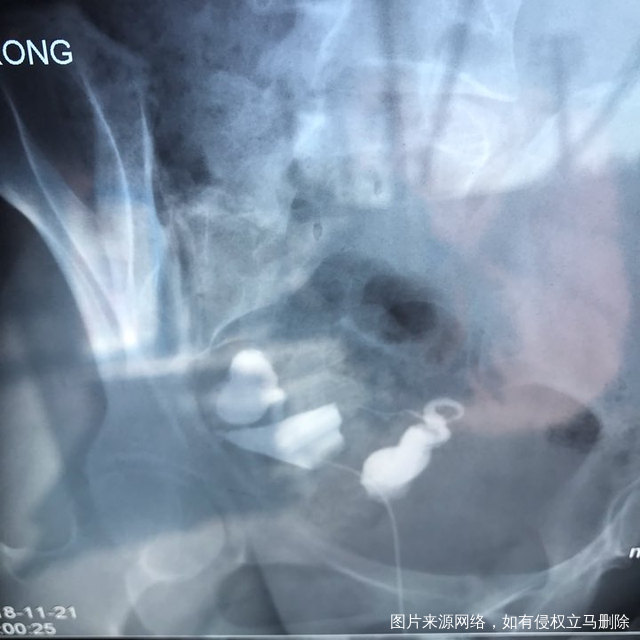

麻烦各位教授给我看看输卵管造影片子,谢谢了🙏